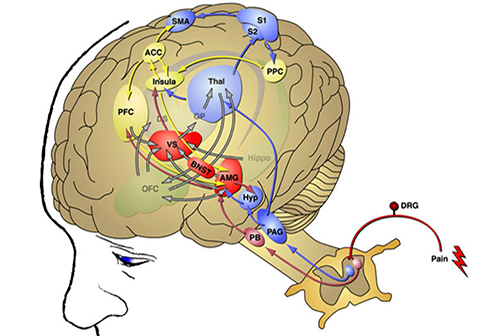

LSU Health New Orleans Study Identifies a Potential New Approach to PTSD Treatment

An LSU Health New Orleans research study led by Siqiong June Liu, PhD, Professor of Cell Biology and Anatomy, has found that cerebellar inhibitory interneurons are essential for fear memory, a type of emotional memory formation. Inhibitory interneurons within the cerebellar circuitry act as gatekeepers and control the output of the cerebellar cortex. The formation of fear memory requires the activity of these interneurons. The findings, which may lead to a novel treatment approach for post-traumatic stress disorder, are published in Cell Reports. More